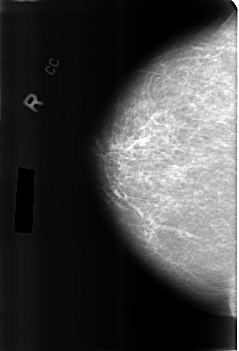

Volume: benign_without_callback_01 Case: B-3214-1

B_3214_1.RIGHT_CC

RIGHT_CC LINES 4560 PIXELS_PER_LINE 3104 BITS_PER_PIXEL 12 RESOLUTION 50 NON_OVERLAY

LESION_TYPE CALCIFICATION TYPE EGGSHELL DISTRIBUTION N/A

ASSESSMENT 2

SUBTLETY 4

PATHOLOGY BENIGN_WITHOUT_CALLBACK

TOTAL_OUTLINES 1

BOUNDARY